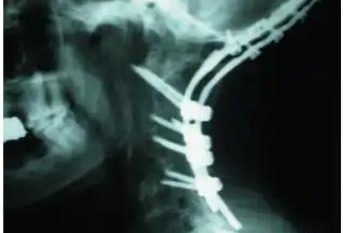

David tiene 22 años, el mayor de 3 hermanos, vive en Venezuela y tiene una condición muy delicada en la cervical, que compromete la médula espinal. Las vertebras C1 y C2 se dañaron, al no tener soporte puede llegar a quebrarse y perder la vida.

Necesita una prótesis para poder sostener su cabeza (foto adjunta) y para ello una operación bastante costosa.